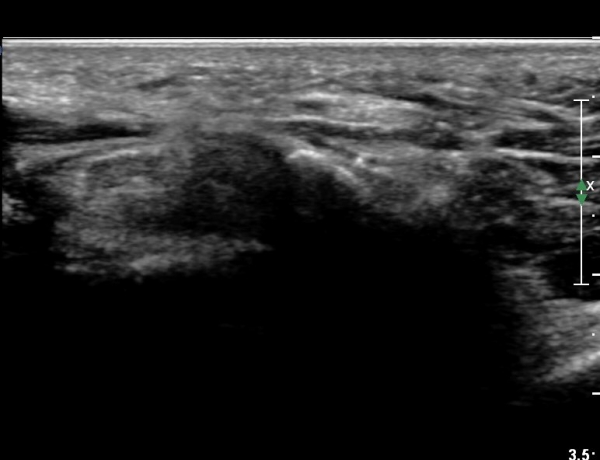

4 sono.jpg